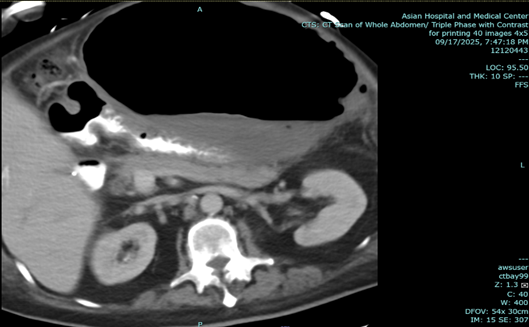

In June 2025, his abdominal CT Scan showed an exophytic lobulated gastric 16.9 x 25 x 17.8 cm mass with central hypodense areas (likely necrosis) arising from fundus and proximal body of stomach, exerting severe mass effect on remaining stomach, pancreas, left hepatic lobes transverse colon, abuts left hemidiaphragm, and distends anterior abdominal wall. Gastroscopy with endoscopic UTS showed a 129.17 x 97.11 mm hypoechoic mass with lobulations at gastric wall adjacent to liver, with some bleeding. Gastric mass biopsy showed GIST, spindle cell type, mitotic rate 4 per 5 mm sq, low grade, CD34+, CD117+, Desmin-, DOG1+, HER-, S100-, Ki67-, 21-30% proliferative index, no loss of nuclear expression of MMR proteins.

Figure 1 a-c: June 29, 2025 Abdominal CT Scan showing hypodense mass.